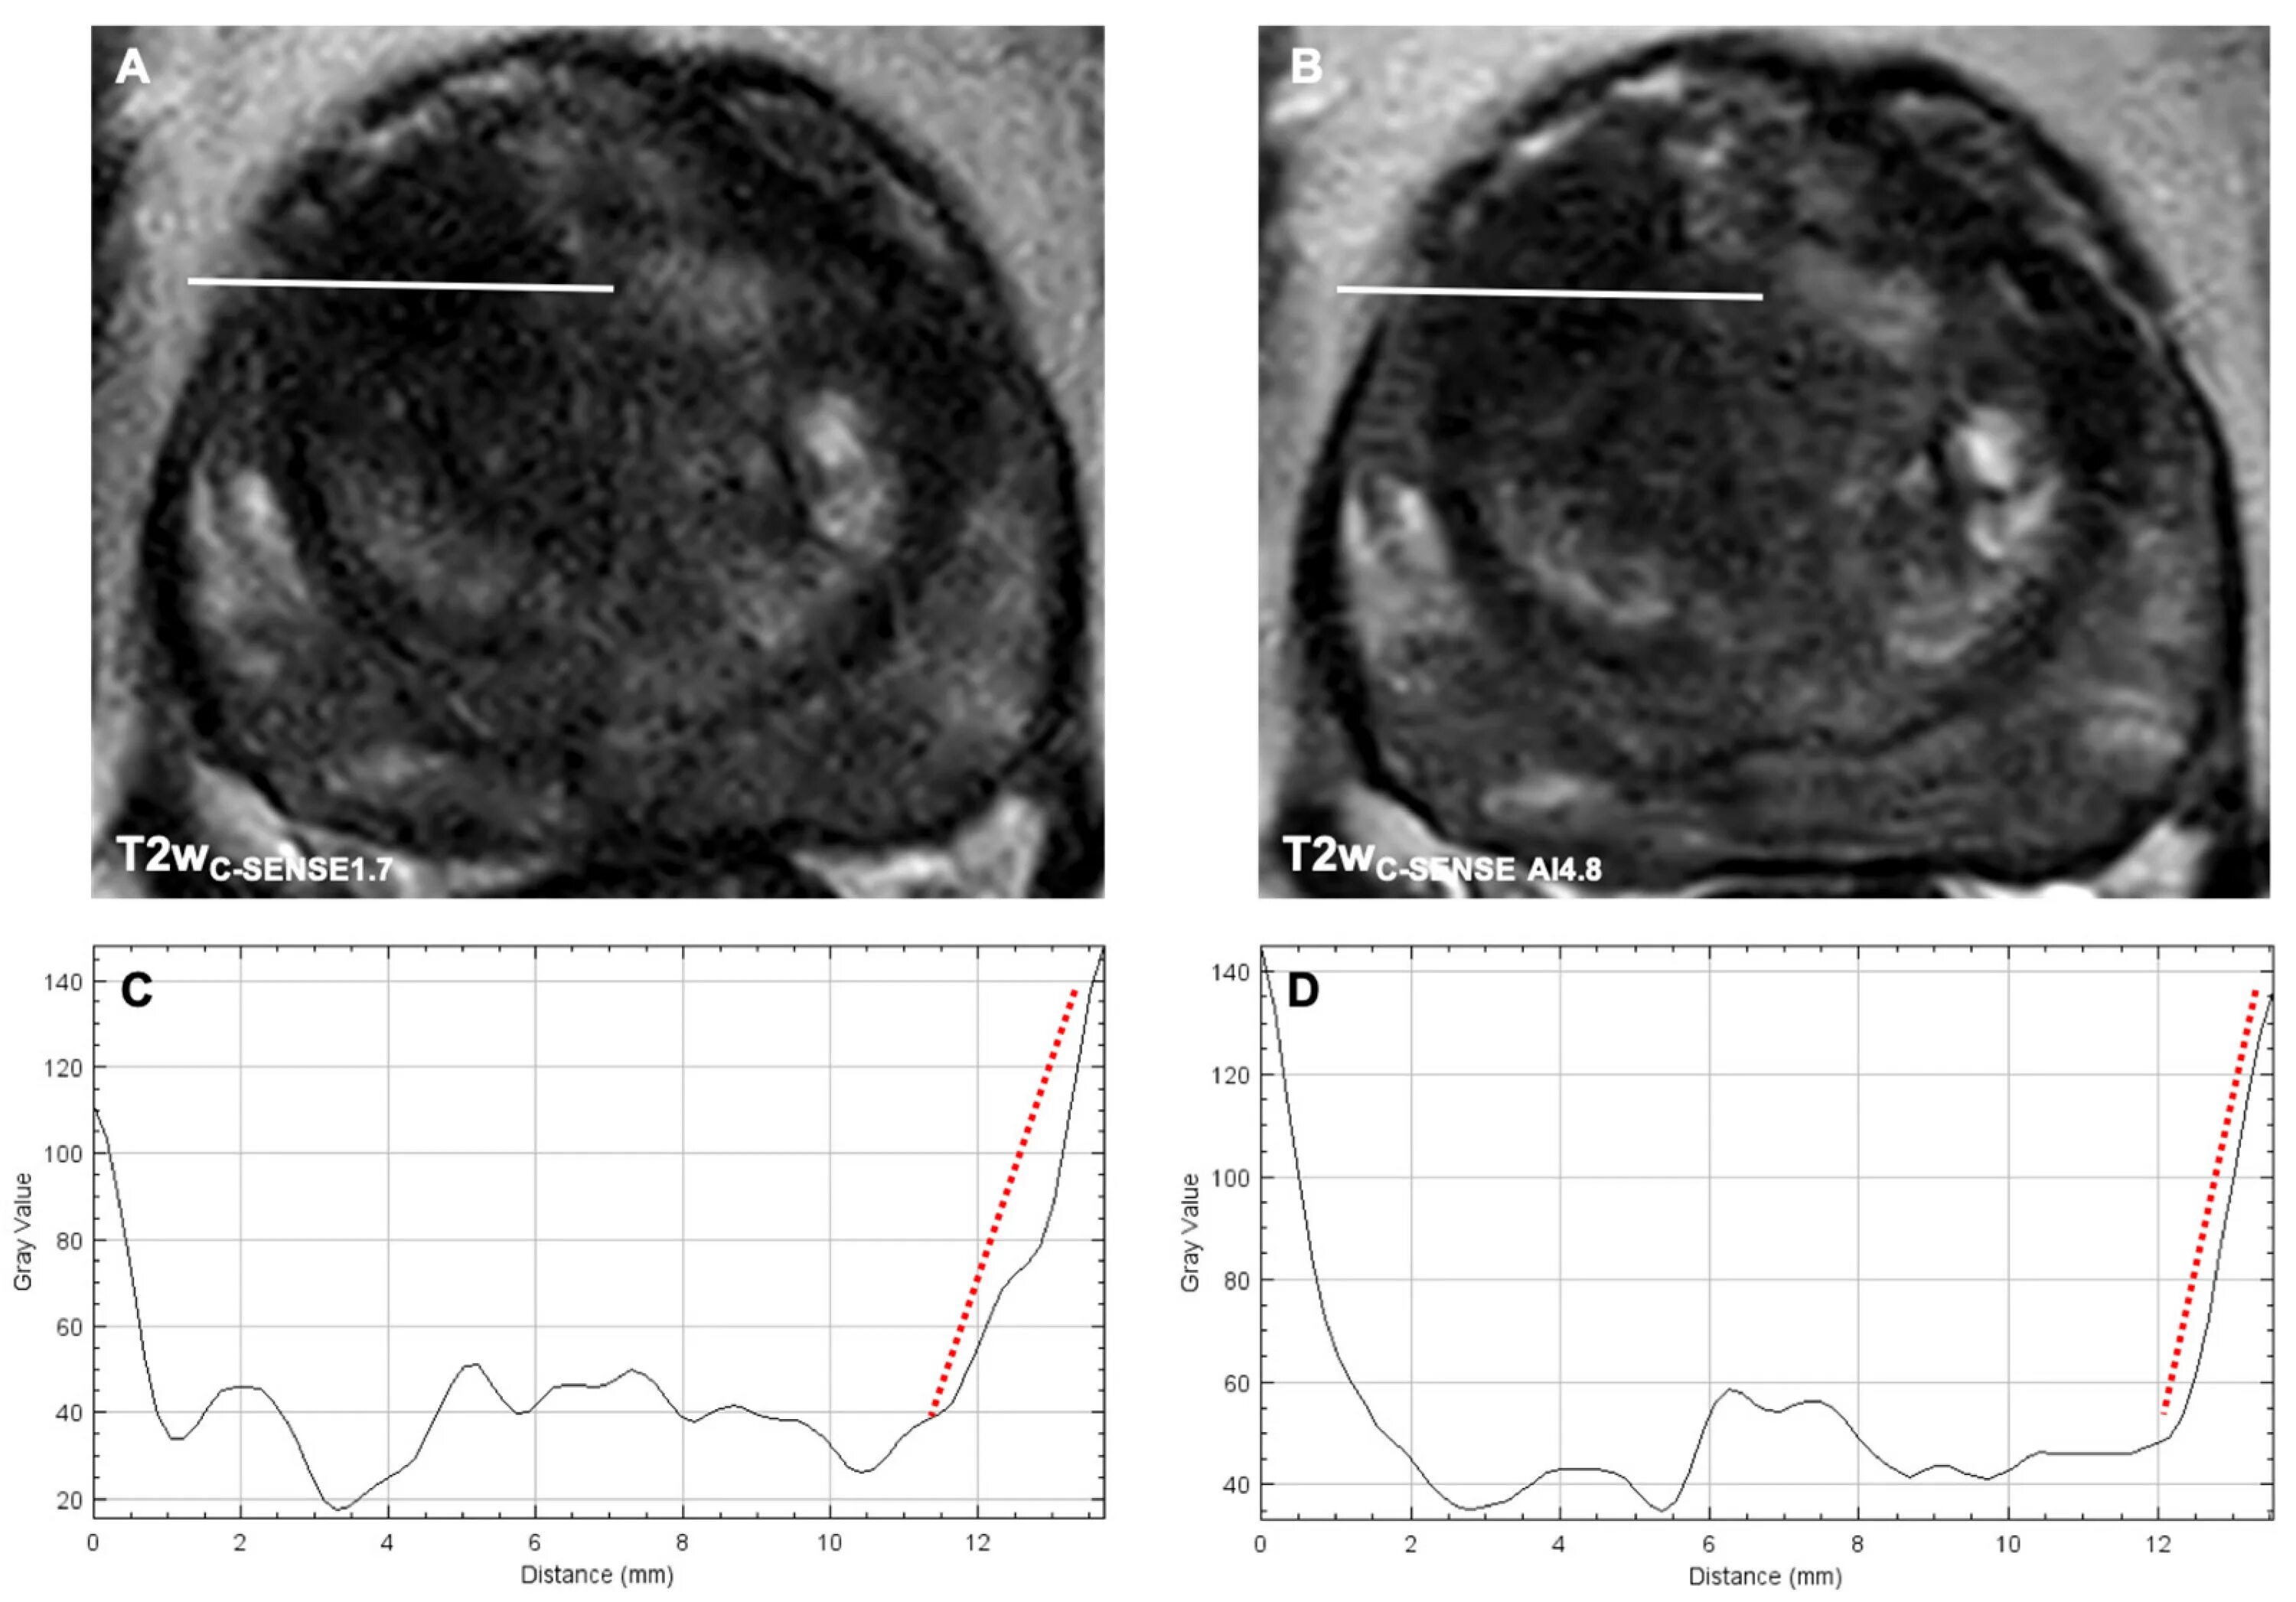

Pi rads v